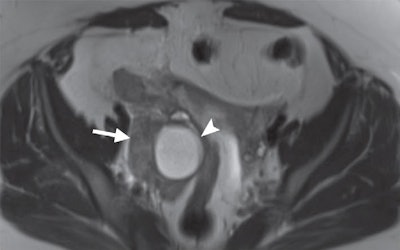

All MRI exams were conducted on a 1.5- or 3-tesla scanner (Magnetom Aera or Magnetom Skyra, Siemens Healthineers) with two 18-channel torso phased-array anterior coils and a 32-channel table-integrated posterior coil to enhance signal reception.

In all, 77 patients went on to the operating room after MRI, based on the scans or other factors such as persistent clinical symptoms. Surgery confirmed 67 cases of acute appendicitis, and of these patients, 65 (97%) had positive MRI results. Among the 10 patients who were negative for appendicitis at surgery, eight (80%) had negative MRI results.

When compared with surgery and clinical follow-up, MRI achieved an overall sensitivity of 97% and specificity of 99%, according to the authors. Positive predictive value was 97% and negative predictive value was 99%.

"MR imaging showed excellent results for the diagnosis of acute appendicitis when compared with surgical results and clinical follow-up," they wrote.